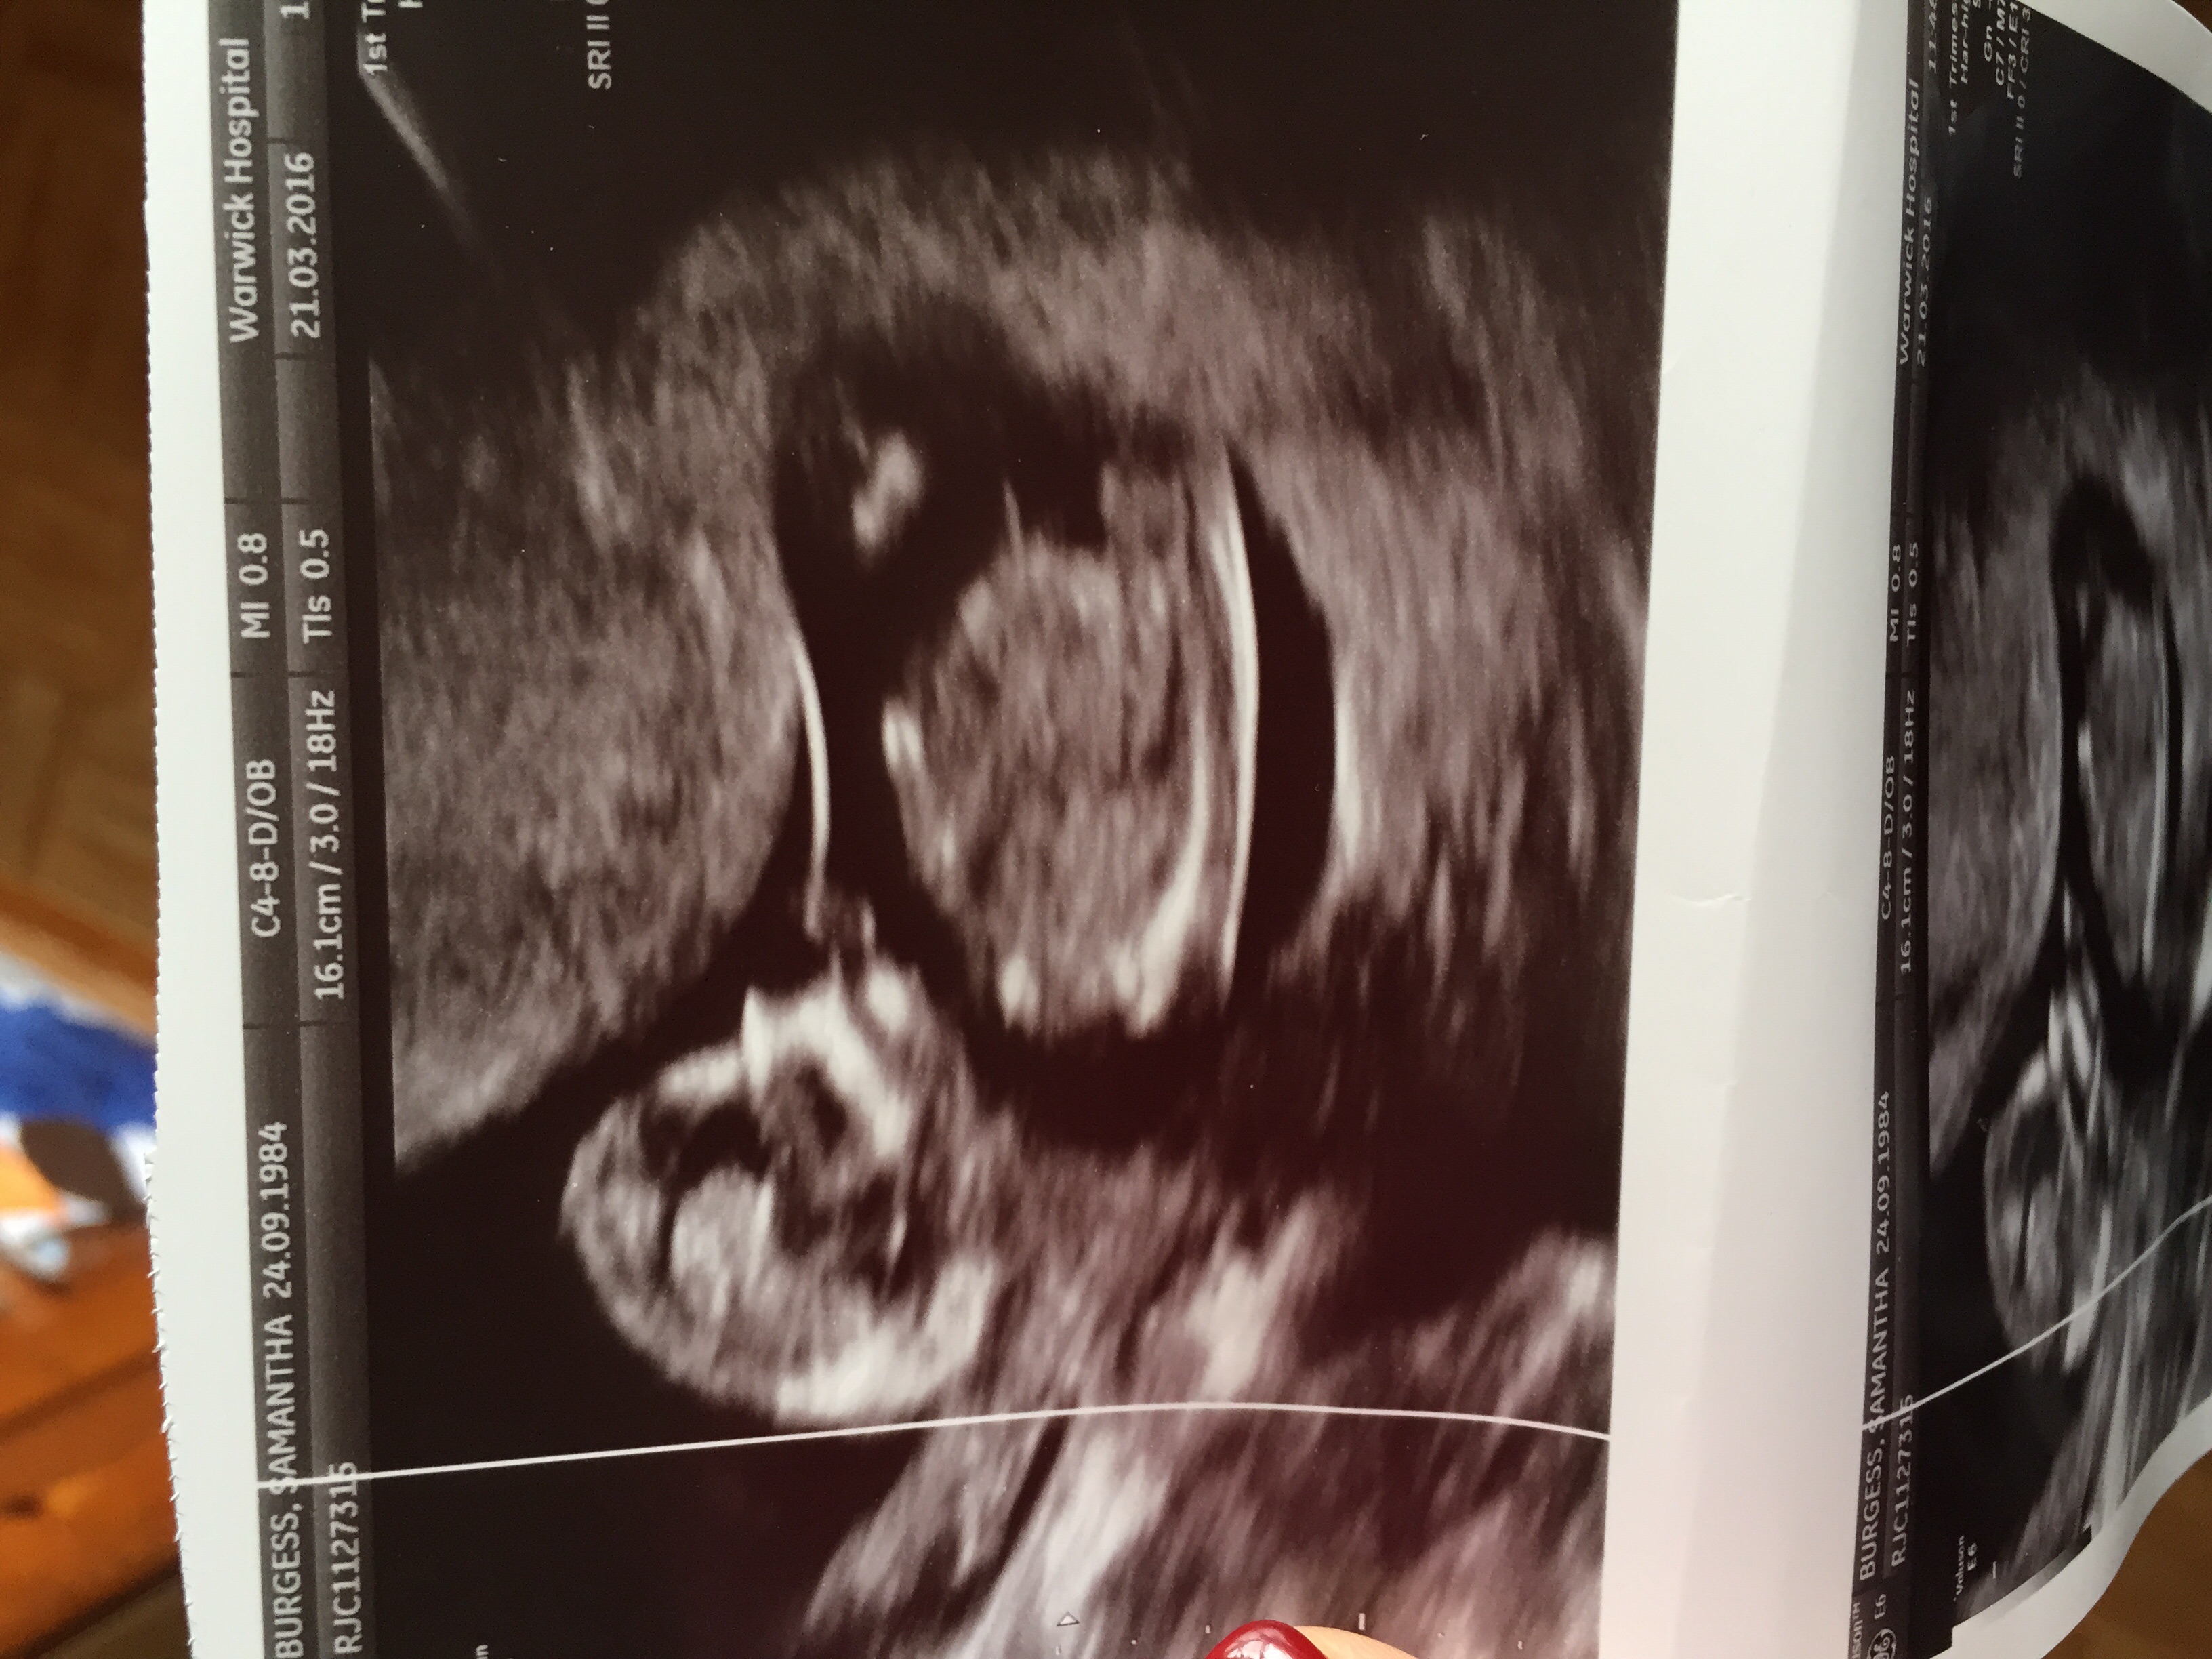

Hi, I'm new to this site and need some help with nub theory. I've had my 12 wk scan and have been googling nub theory. I've looked at my pic and I can see two lines one near the genital area up from the spine and one closer to the belly. Uploaded my scan pic can anyone help please??Which one is the nub??Attachment 30908

Sorry I don't think you've got a visible nub shot here

Thanks family Matters. Any clues to what the long straight line is at the top??

Not sure to be honest, but it's not the nub I know that :)